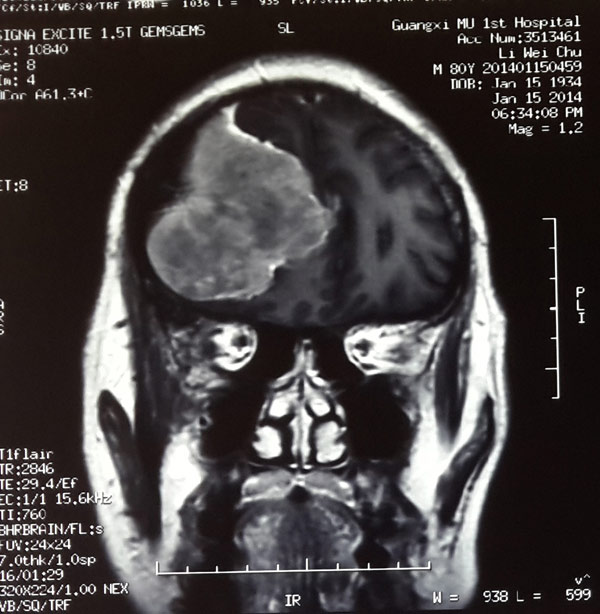

头颅CT显示,李大爷颅内肿瘤已经长至鸭蛋大小,立即手术是挽救老人生命的唯一办法。

术前可见巨大脑膜瘤